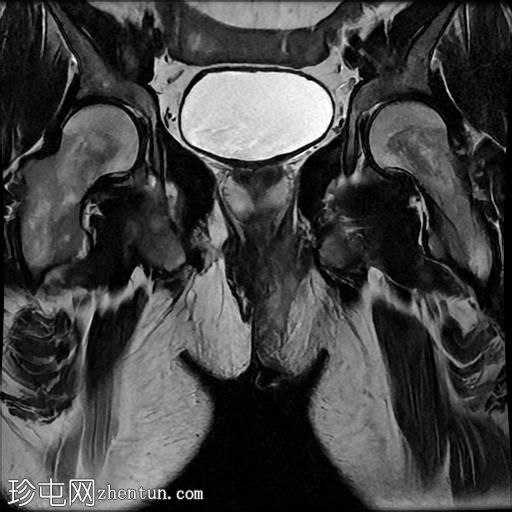

MRI

轴向位T2

脂肪饱和度

冠状位T1

一条68毫米厚的强化通道始于左侧肛周区域,向上穿过肛门内外括约肌,在2点钟方向开口于肛管。

无脓肿形成。

MRI成像特征与所述左侧经括约肌肛周瘘相符。